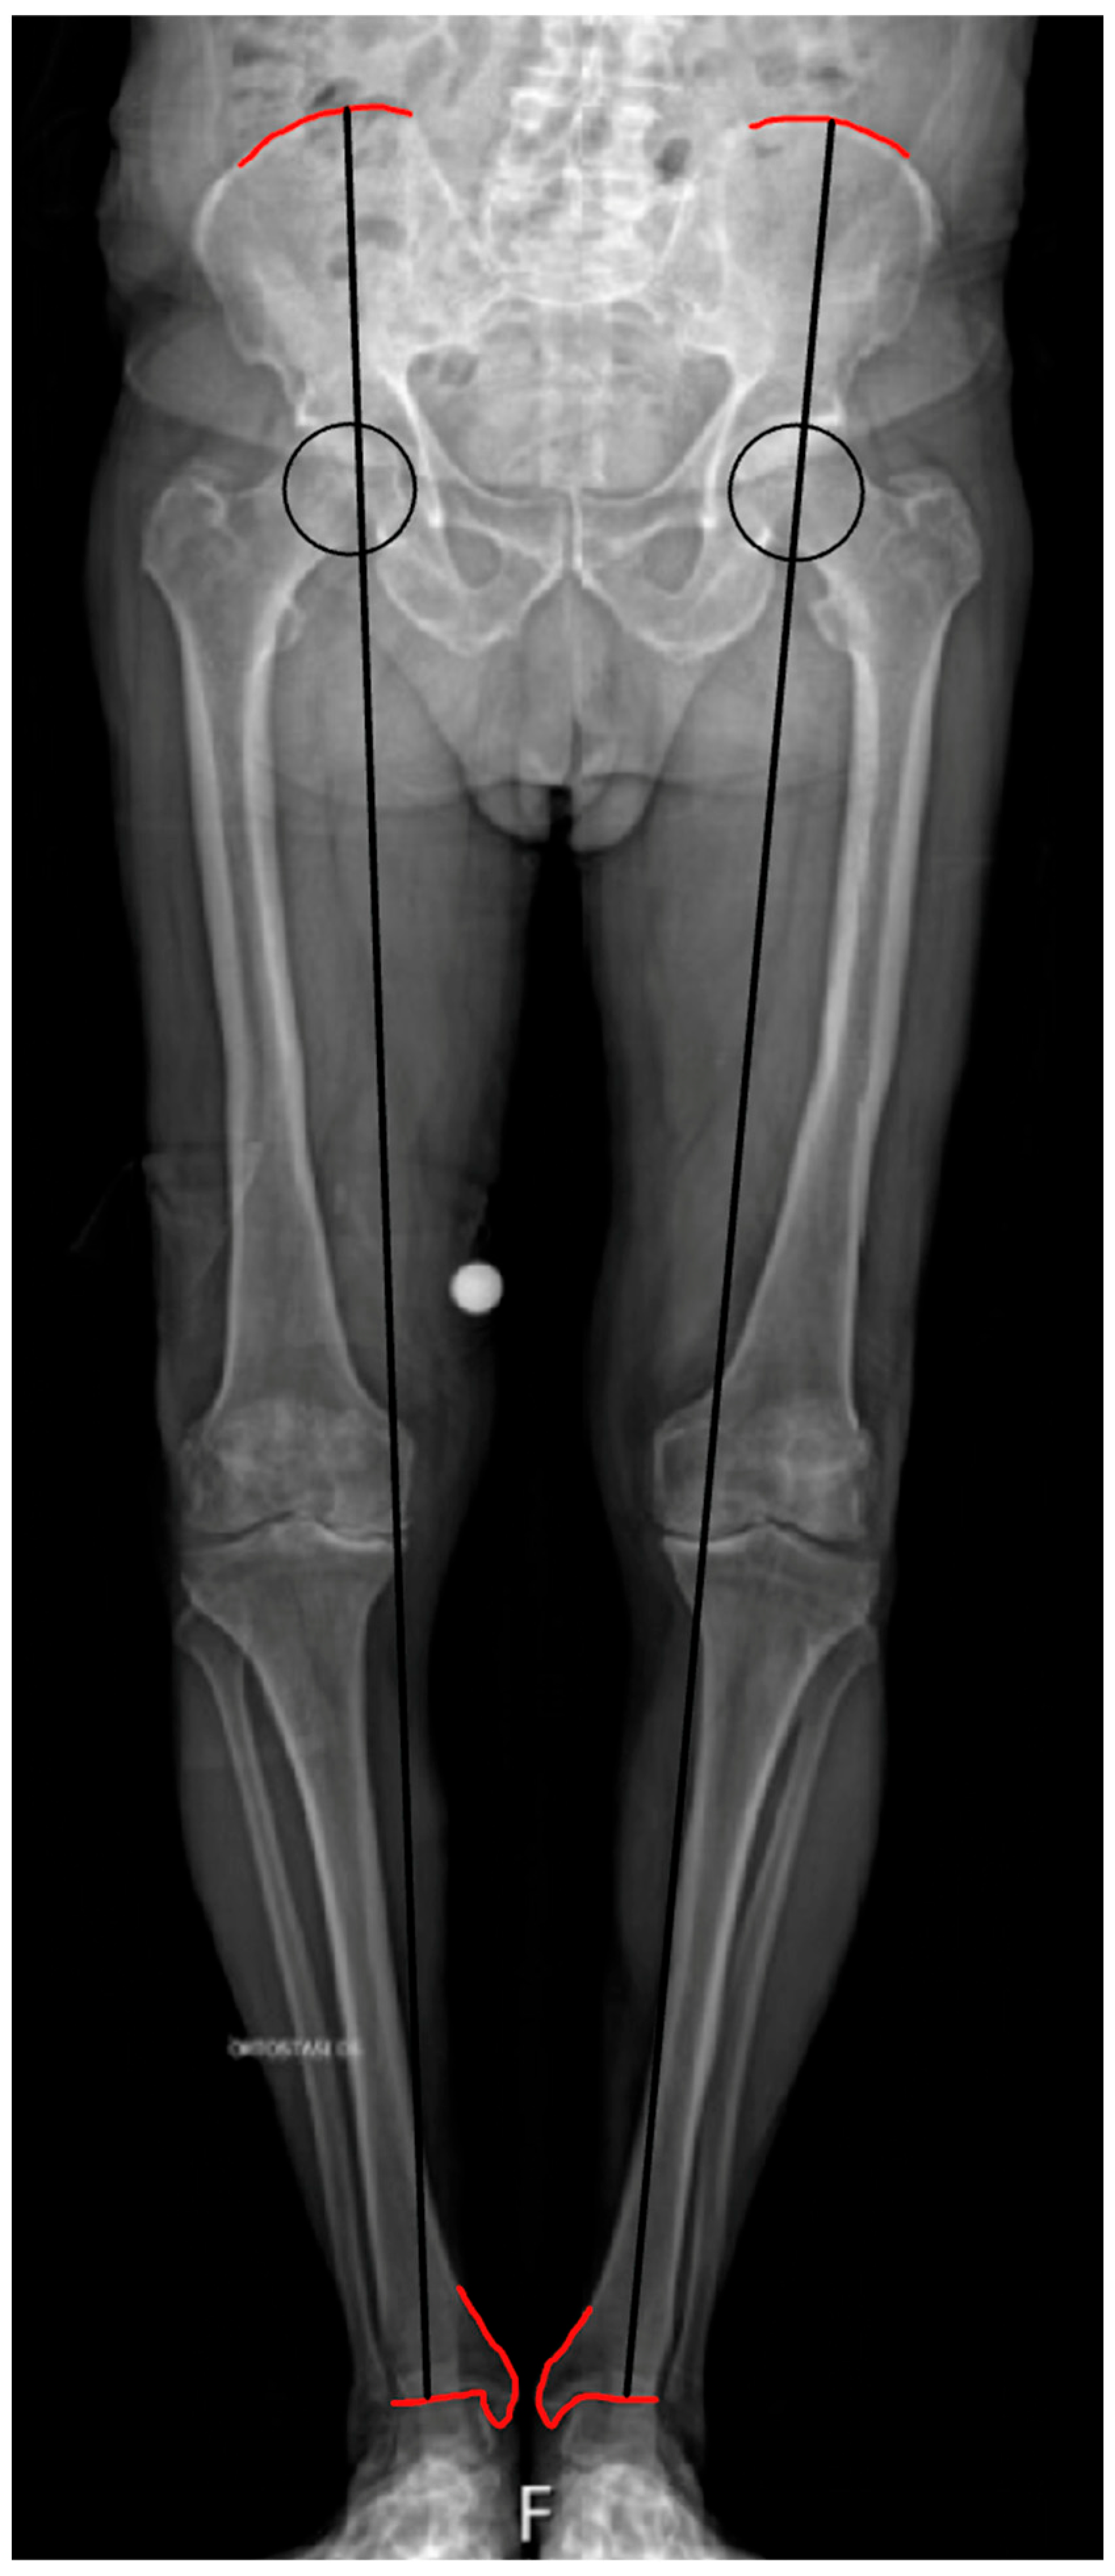

2. Anatomical and Functional Lower Limb Discrepancy: Definition and Assessment

3. Lower Limb Discrepancy in THA

4. Preoperative Planning and Intraoperative Assessment